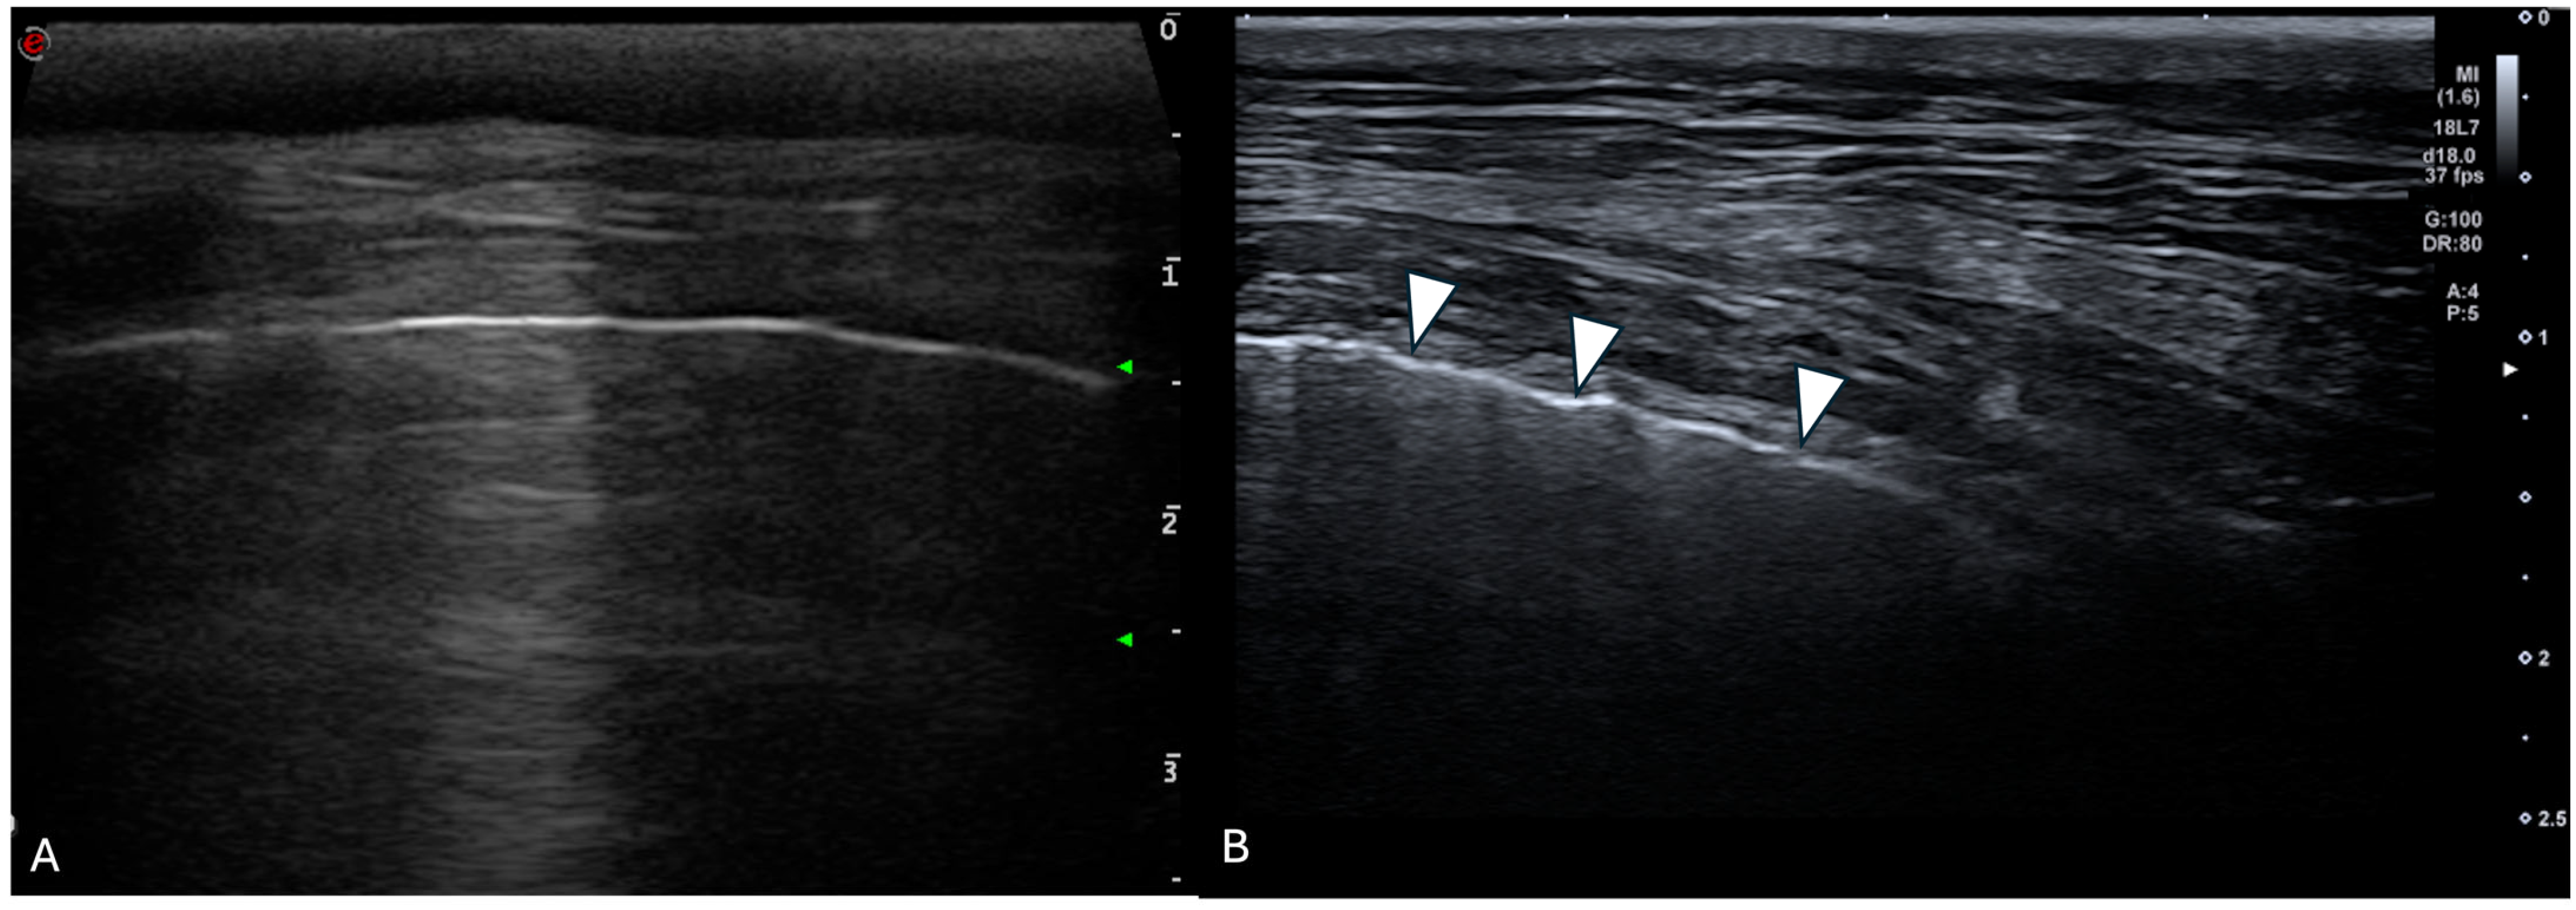

2.1. Thoracic Ultrasonography

3.3.1. Transducers

3.3.3. Ring-Down Artefacts

3.3.4. Pleural Surface